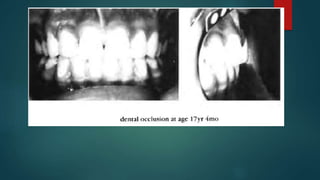

Case 1 (age 8yr 4mo), cephalometric diagram. Broken line outlines

average female face at age 7yr 7mo ± 18mo. Superimposition is on

Nasion, oriented on Frankfort horizontal. Black indicates patient

outside the average outline, shading indicates patient inside the

average outline.

Dental occlusion shows crossbite o f the incisors, deep overbite and

noticeable underjet. This patient was treated with a chin cap and

intraoral appliance. The figure below shows the occlusion on the final

record taken at the age o f 17 years and 4 months. The cephalometric

diagram shows the size and position o f the mandible to be fairly well

balanced, yet the middle face is still retarded in relation to the normal

pattern.